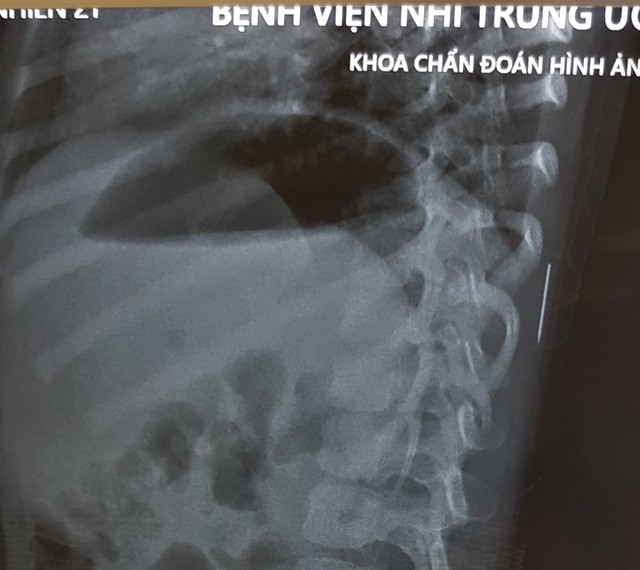

Tại Bệnh viện, các bác sĩ đã chụp Xquang và phát hiện một dị vật nằm trong phần mềm vùng cơ lưng trái, đốt sống 11 của bé.

| Hình ảnh X-quang chiếc kim khâu trong cơ thể bệnh nhi (Ảnh: BVCC) |

Sau 1 tiếng đồng hồ phẫu thuật, các bác sĩ đã lấy ra dị vật nằm trong cơ thể bé là ½ của chiếc kim khâu dài 17mm đã bị gỉ đen. 3 ngày sau phẫu thuật, sức khỏe bé M. đã ổn định, sẽ được ra viện trong vài ngày tới.